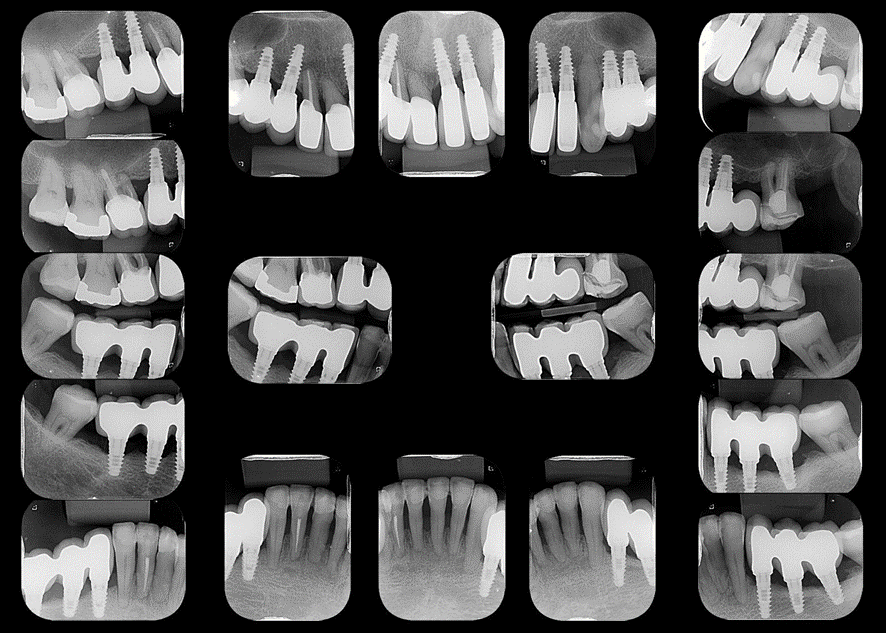

Esta abordagem permitiu, em 2018, o diagnóstico de doença peri-implantar no implante colocado na região do dente 36 e, posteriormente ao tratamento desta condição, pode-se observar a estabilidade do nível ósseo nos acompanhamentos radiográficos nos anos de 2021 e 2023.

O acompanhamento longitudinal desta paciente ilustra a possibilidade de manutenção de dentes, mesmo com suporte periodontal reduzido, associada a reabilitação implantossuportada. Neste tipo de abordagem, a terapia periodontal age de forma sinérgica à reabilitação implantossuportada, garantindo o sucesso do tratamento reabilitador, desde que os pacientes realizem controles periódicos.

Este caso evidencia que, com manutenção periodontal regular e adequada, é possível manter dentes com suporte reduzido e reabilitar o paciente com histórico de doença periodontal com implantes de forma estável e funcional. Para isso, é fundamental a adesão do paciente ao plano de manutenção para garantir o sucesso a longo prazo tanto dos dentes quanto dos implantes.